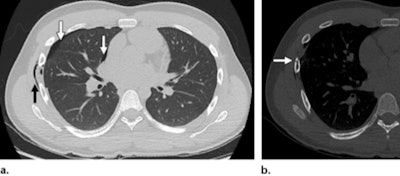

Biyyam's team listed the following injuries caused by handlebar trauma that can be diagnosed with CT and described some of the findings' characteristics.

- Thoracic: Rib fractures, pneumothorax, pulmonary contusion, pneumomediastinum

- Abdominal: Pancreas, small bowel, mesentery, liver, spleen, adrenal gland (liver lacerations may present as linear hypoattenuating lesions; spleen lacerations range from linear to branching patterns)